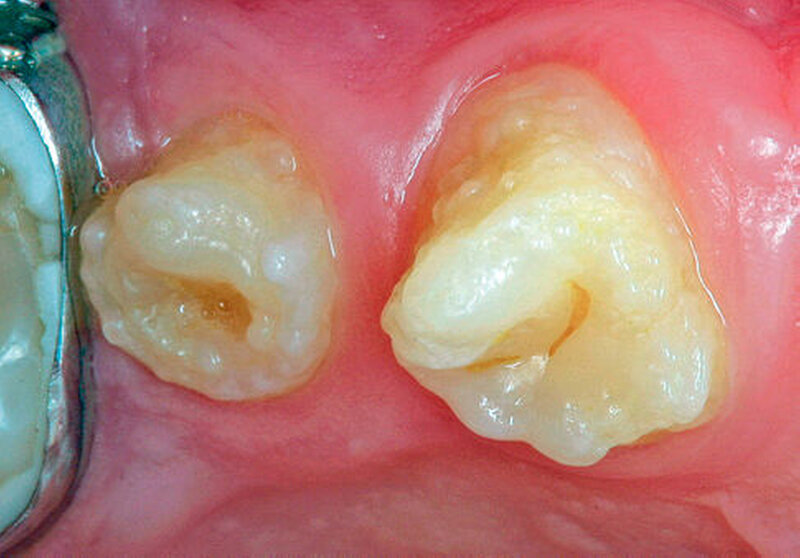

Bei dieser genetisch bedingten Schmelzdysplasie sind in der Regel alle Zähne einer oder beider Dentitionen betroffen, und es ist ein bilateralsymmetrisches Erscheinungsbild vorhanden. Die Ausprägung der Schmelzdefekte kann von Zahn zu Zahn und von Generation zu Generation variieren (Abbildungen 1a bis 1c). Die Struktur des Dentins ist nicht verändert. Die Schmelzdefekte treten als Grübchen von unterschiedlicher Größe in mehr oder weniger normal dickem Schmelz in Erscheinung (Abbildung 2a). Durch Einlagerung von Farbstoffen in diese Grübchen können die Schmelzveränderungen ästhetisch störend wirken (Abbildung 2b). Ähnliche grübchenartige Schmelzhypoplasien können bei Patienten mit Rachitis, Pseudohypoparathyroidismus oder Epidermolysis bullosa beobachtet werden. Bei der hypoplastischen Form der Amelogenesis imperfecta ist die Schmelzhärte normal, die Schmelzdicke jedoch reduziert. Der grübchenartige Typ weist als Ausnahme eine fast normale Schmelzdicke auf (Abbildungen 3 und 4).

Die Amelogenesis imperfecta kann neben der hypoplastischen Form in eine hypomaturierte Form und eine hypokalzifizierte Form eingeteilt werden. Auch Kombinationen der verschiedenen Formen der Amelogenesis imperfecta wurden beschrieben. Bei der hypomaturierten Form ist die Schmelzhärte weicher als normal, die Schmelzdicke entspricht beim Durchbruch der Zähne der Norm. Bei der hypokalzifizierten Form ist der Schmelz sehr weich und die Schmelzdicke beim Zahndurchbruch normal. Deshalb sind vor allem bei der hypomaturierten und hypokalzifizierten Form die Abrasion und Attrition stark erhöht. Bei beiden Formen ist die Zahnfarbe beim Durchbruch der Zähne opakweiß bis gelblich. Mit zunehmendem Alter werden die Zähne braun. Die Prävalenz der Amelogenesis imperfecta beträgt je nach Population und Typ zwischen 1: 700 bis 1 : 20.000.